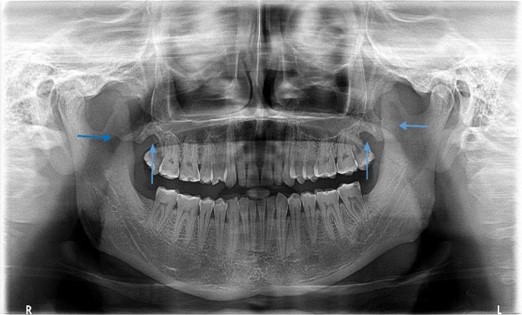

A panoramic radiograph showing a fracture involving the mandibular angle. What potential complication should be assessed, and what intervention is needed?

Image of a panoramic radiograph. What condition may be suspected if an air-fluid level is observed within the maxillary sinus?

This is an image of a panoramic radiograph. What radiopaque structure is indicative of the maxillary sinus, and where is it typically located?

A panoramic radiograph showing radiolucency within the maxillary sinus. What could be a potential finding, and what further evaluation is needed?